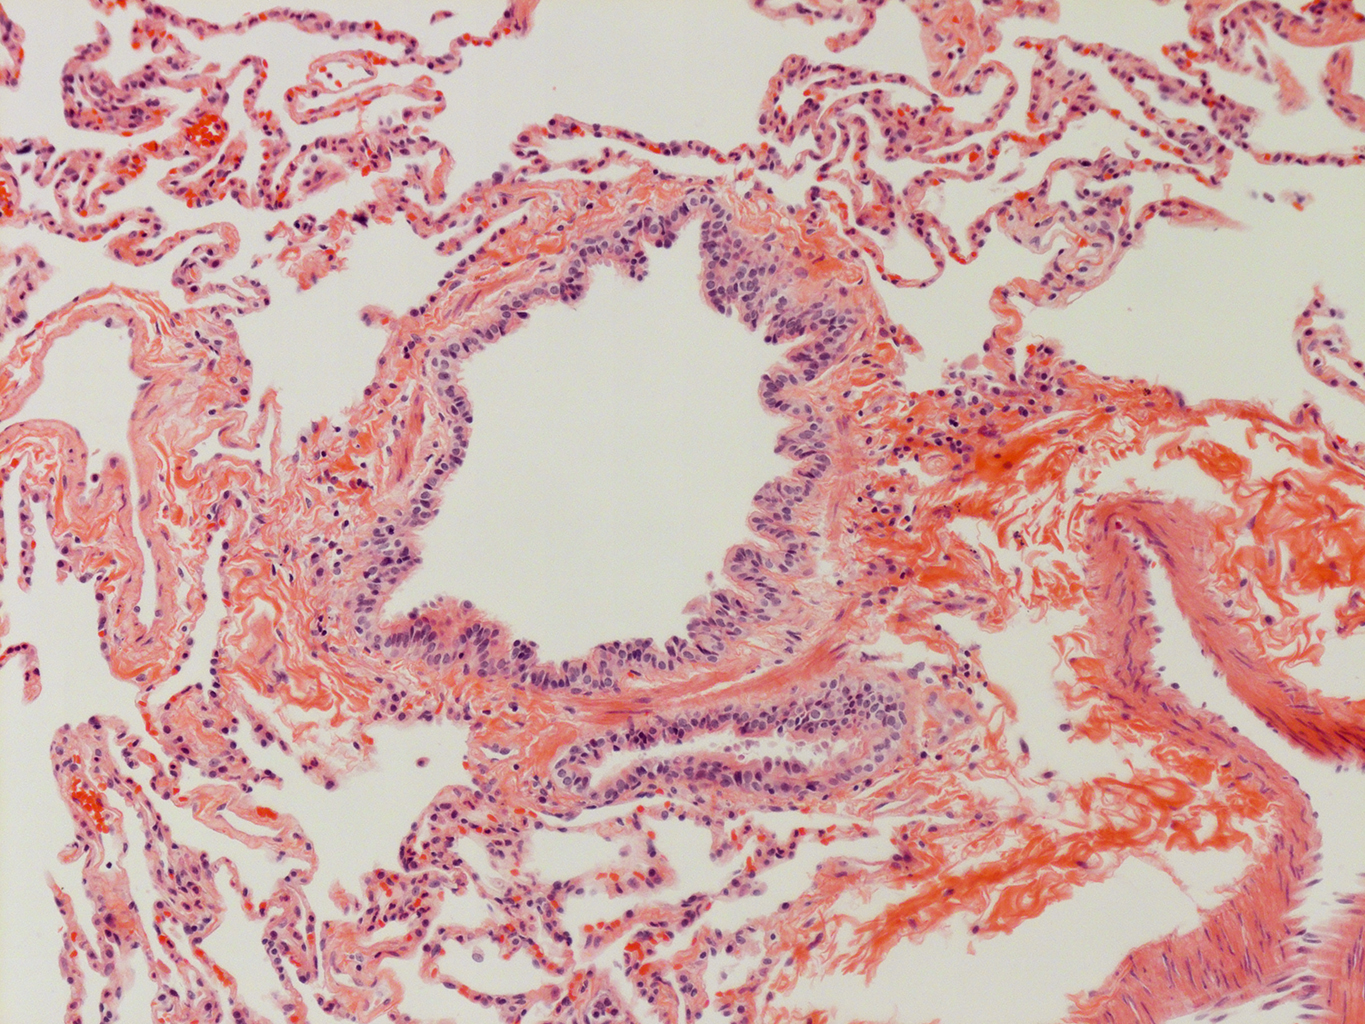

Donor tissue kindly provided by Dr. Scott Randell, University of North Carolina

Tissue Used:

LMHA-15-UNC-2017-12-19_D0037L.05HP_3_48

Gender: Male

Age:Â 43 Year Old

Race: Hispanic

Non-Smoker